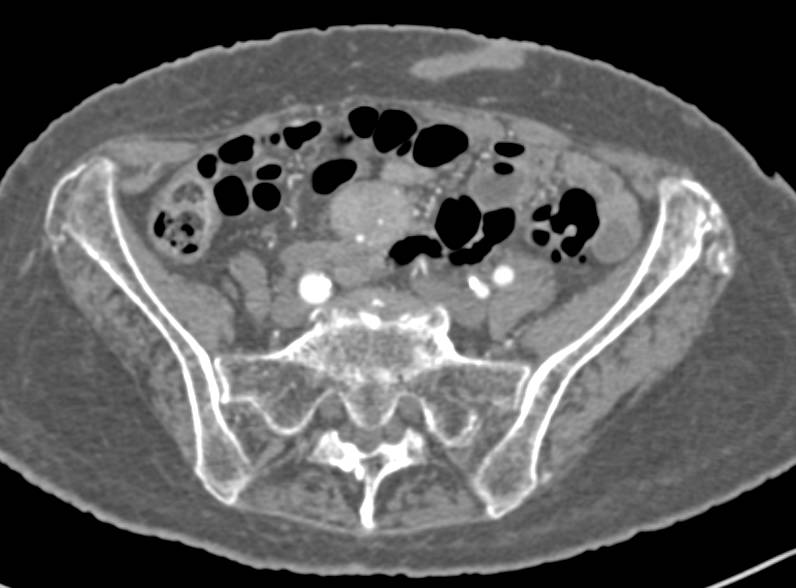

Necrotic Duodenal Adenocarcinoma with Liver Metastases